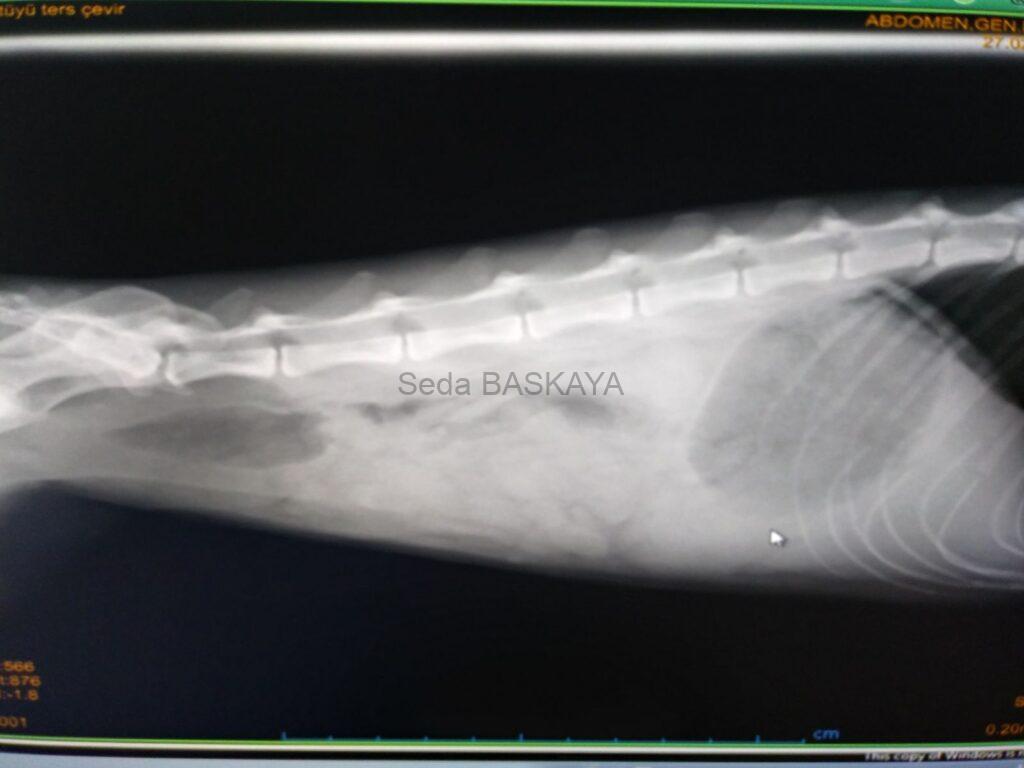

Radiography (x-ray):Whether there are stones in the urinary tract and bladder is determined by x-rays.